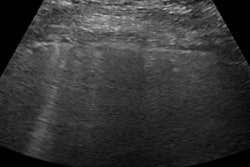

They used an eight-zone lung ultrasound protocol and categorized predefined abnormalities as subpleural consolidations, irregular pleural lines, or pleural effusion.

Investigators enrolled 143 patients with signs and symptoms of COVID-19. A total of 70 had both a positive lung ultrasound and positive chest x-ray. Of those, 58 had positive CT findings suggestive of atypical viral pneumonia.

A total of 42 patients had a positive lung ultrasound and negative chest x-ray. Of those, 23 had positive CT findings. Six patients had a negative lung ultrasound and a positive chest x-ray, but none of the six had a positive CT finding. Twenty-five patients had both a negative lung ultrasound and negative chest x-ray. Still, seven of them advanced to CT imaging because they had one or more high-risk features, such as the presence of immunosuppression or lymphopenia. Two of the seven had a positive CT.

Lung ultrasound recorded higher sensitivity than chest x-ray, the researchers found.

| Sensitivity | 69.9% | 97.6% |

| Specificity | 44.4% | 33.3% |

"Lung ultrasound is more sensitive than chest x-ray," said Dr. Mendez. "Both modalities had poor specificity."